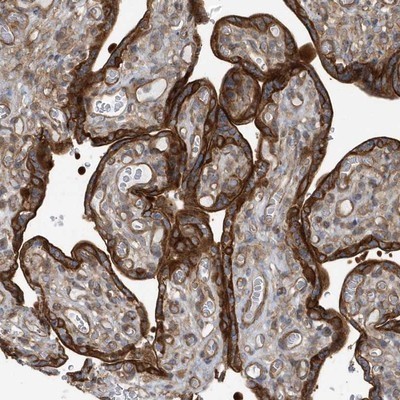

- Main image

- Experimental details

- Immunohistochemistry-Paraffin: RAI14 Antibody [NBP1-94076] - Staining of human placenta shows strong membrane and cytoplasmic positivity in trophoblastic cells.